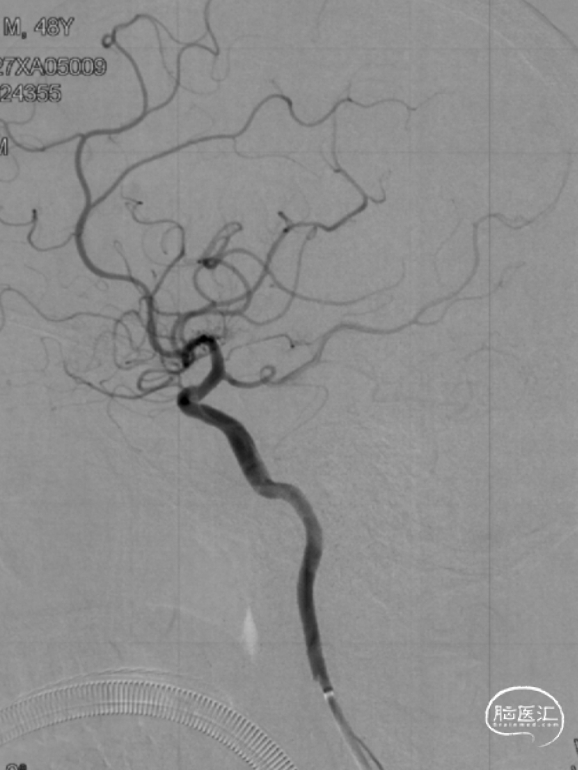

撤出导管导丝后造影,可见靶血管支架贴壁良好,前向血流通畅稳定。

术后行Dyna-CT未见异常,支架定位准确,贴壁良好。

再次造影观察,确认手术成功,结束手术。

复查脑血管造影示:右侧大脑中动脉支架置入术后,支架位置良好,管腔内血流通畅,未见明显狭窄。

2023-02-06 6M-FU (正位)

2023-02-06 6M-FU (侧位)